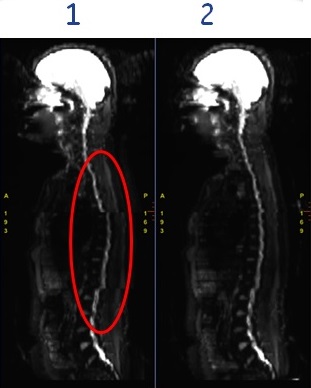

- To reduce station-to-station misalignment in whole body diffusion imaging.

Figure 4. Real Time Center Frequency on/off affects on station-to-station alignment

Table 3. Image legend Number Description 1 Image acquired with Real Time Center Frequency option turned Off. The circle indicates the area of poor alignment.

2 Image acquired with Real Time Center Frequency option turned On. Note the improved station-to-station alignment.